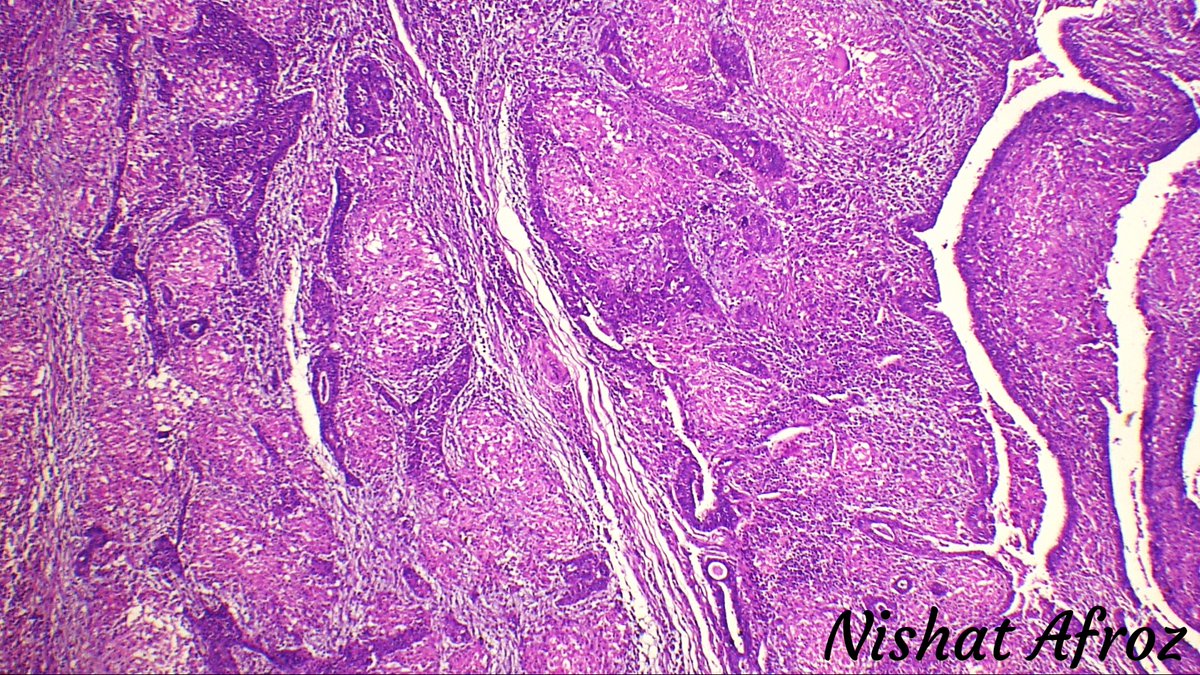

Intracholecystic papillary neoplasm:

Gallbladder counterpart of pancreatic IPMN.

Needs thorough sampling to rule out invasion (I do total embedding), which is the most important point.

Can show adjacent flat dysplasia (sample that too!).

(1/2)#GiPath#GrossPath#Pathology pic.twitter.com/aaEopqefBF